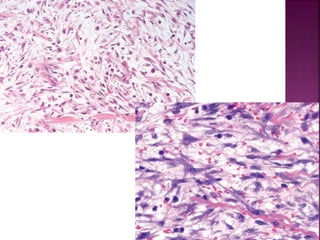

Fibrosarcoma

 Pueden aparecer en cualquier parte del cuerpo

 Preferencia MI

 Masas en carne de pescado

 Masas encapsuladas, infiltrantes, consistencia

blanda y elástica

 Hemorragia y necrosis

 Crecimiento lento, Agresivos,

 50% recidivan, 25% metastiza